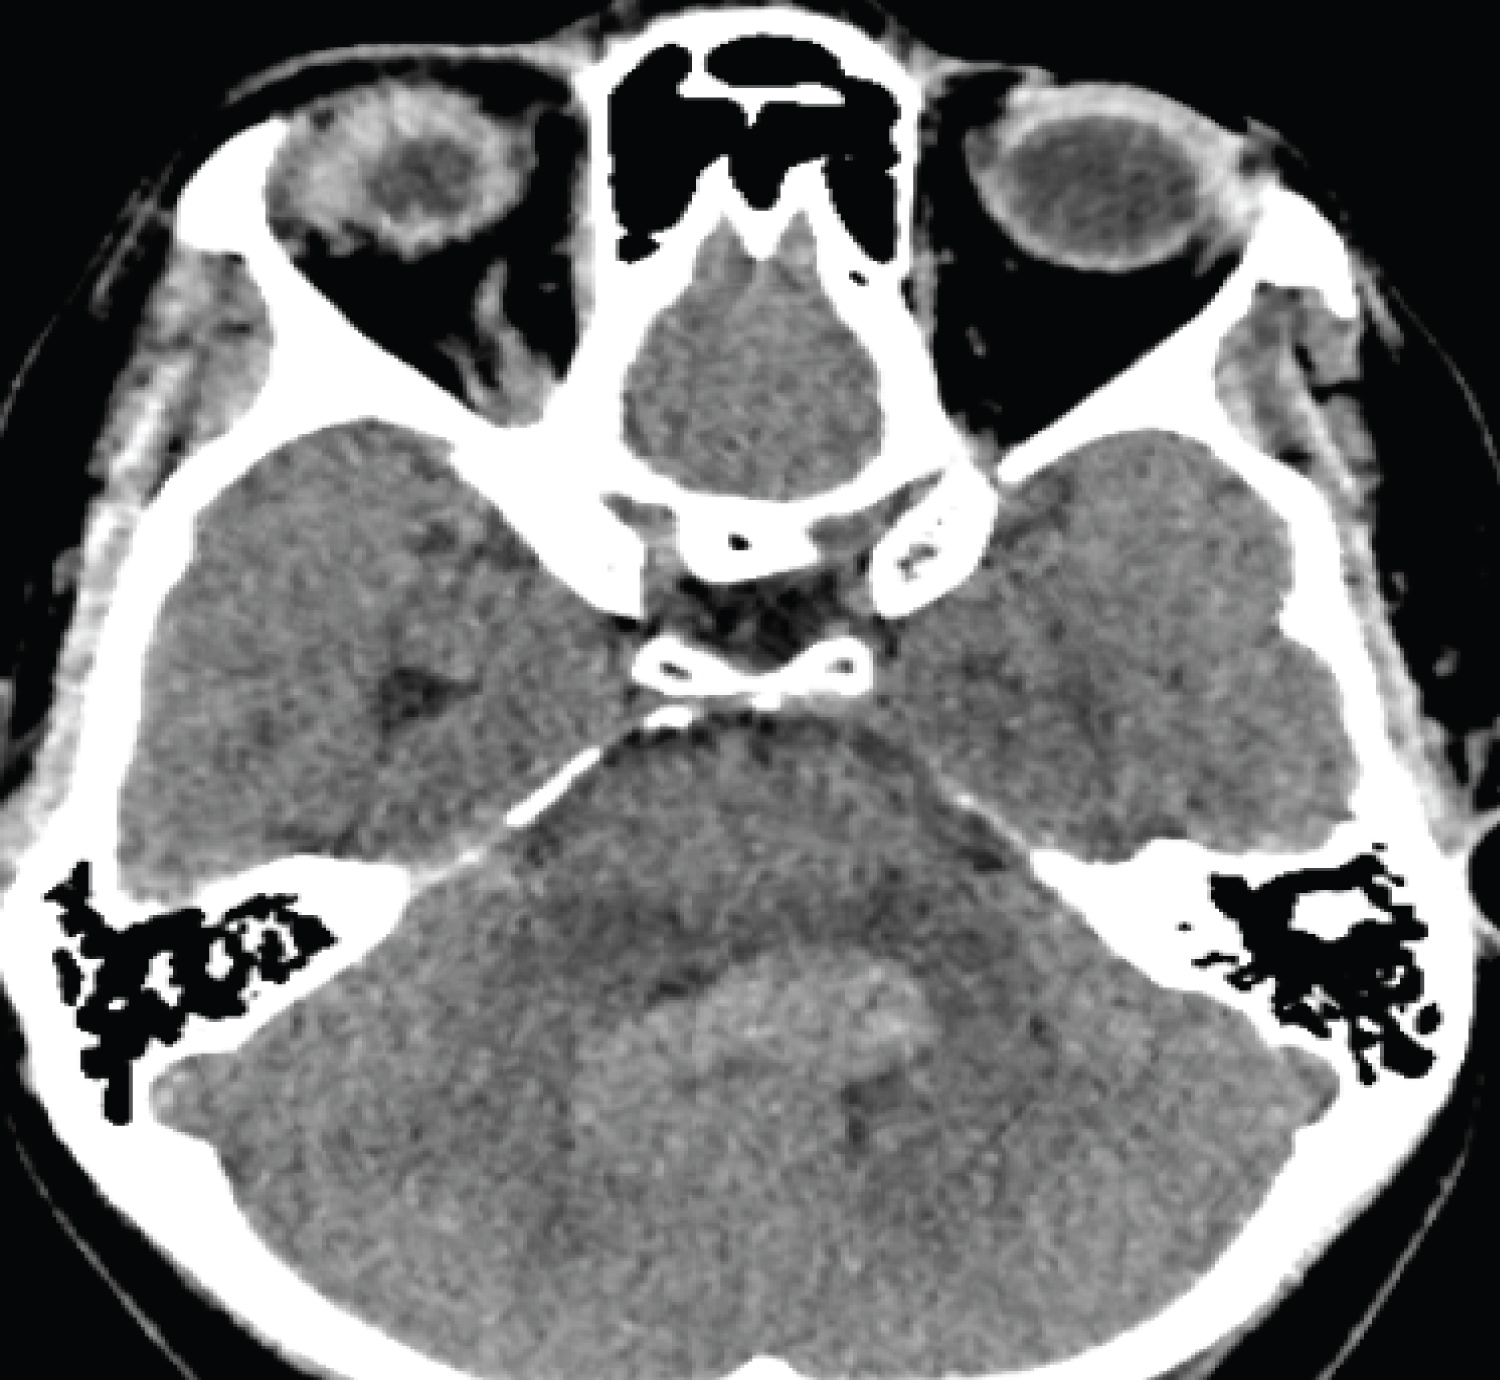

Due to her symptomatology, a plain brain CT scan was performed. This revealed a hyperdense mass lesion in the fourth ventricle, which measures 32 × 28 mm with some degree of obstructive hydrocephalus. CT with contrast revealed an avidly enhancing mass lesion filling the fourth ventricle (Figure 1).

Figure 1: Non-contrast CT brain showing 4th Ventricular mass lesion. View Figure 1

The lesion was initially thought to be a 4th ventricular tumour with ependymoma as top radiological differential. She was then transferred to our unit for further evaluation and management.

On arrival to our unit, we performed MRI sequences which include T2 weighted, susceptibility weighted, and T1 volume pre-and post-contrast and 3-D time-of-flight MRA. These showed a serpiginous lesion within the fourth ventricle that exhibited a flow void on T2-weighted imaging and appears to arise from terminal left posterior inferior cerebellar artery (Figure 2 and Figure 3).

Figure 2: MRI T1- pre-contrast axial and sagittal showing the mixed intensity 4th Ventricular tumour. View Figure 2